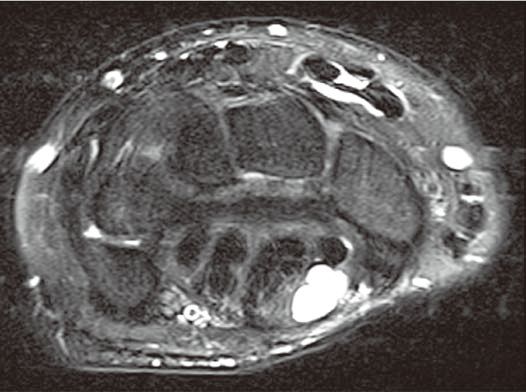

图2腕管腱鞘囊肿

A

B

C

横轴位(A)和冠状位(B)脂肪抑制T2WI示腕管内较大的腱鞘囊肿,内含液体而呈高信号。冠状位脂肪抑制增强T1WI(C)示囊壁强化而囊液不强化